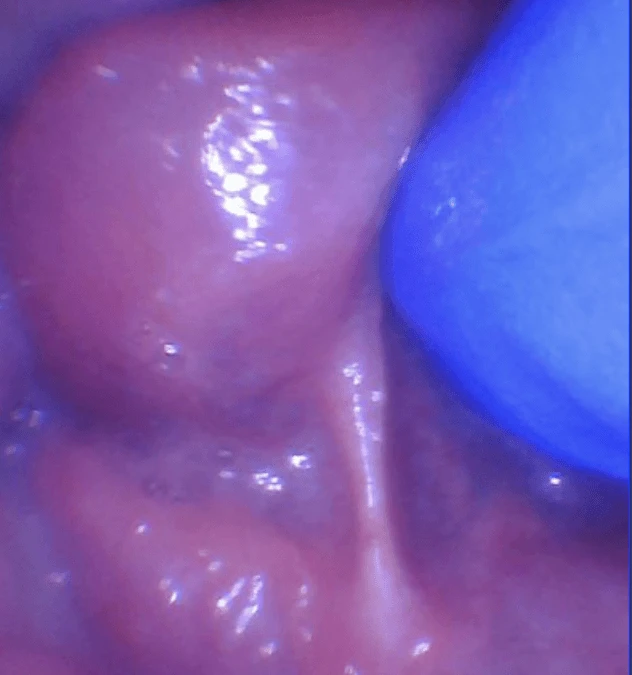

Myth #1: “They will just laser everyone.”  First off, we do not use a lightsaber! We use an ultra-precise surgical CO2 laser that looks like a pen and doesn’t even touch the tissue. It removes tissue layer by layer, and allows us to see all the...